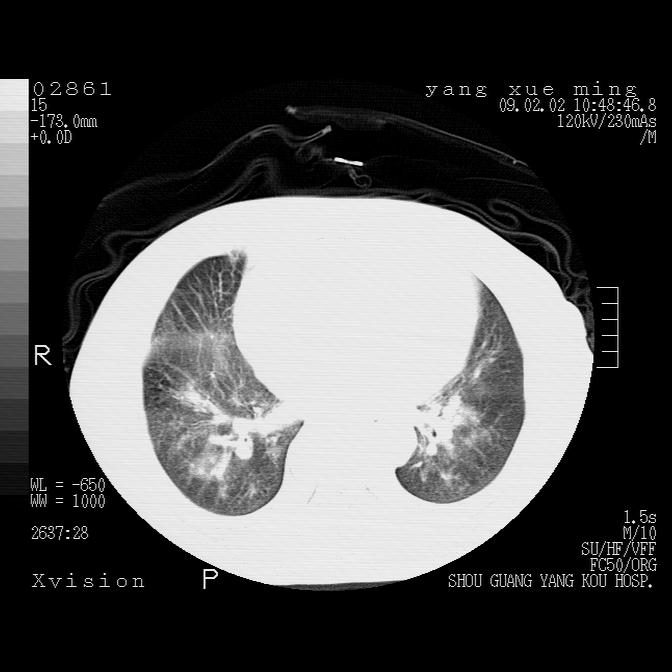

以下是引用lkc8963在2009-2-3 20:11:00的发言:[br]1)右上肺陈旧病灶。2)右下肺团块及团片影,影像表现符合感染。3)左心增大,左冠脉钙化,符合冠心病。4)双侧肺门扩大,以左侧为著,肺动脉干略粗,左上肺局限性气肿,为谨慎起见,需除肿瘤,建议增强。

以下是引用zbp537在2009-2-3 19:08:00的发言:[br]我诊断为肺泡性肺水肿。[br]诊断依据:[br]1、心影普遍增大,肺血管增粗,并见絮状高密度影,肺门改变显著。[br]2、临床上表现胸闷咳嗽,无发烧,不是一个典型的肺部感染的病史。

以下是引用王仕学在2009-2-3 20:28:00的发言:[br]考虑右下肺感染,建议治疗后复查。